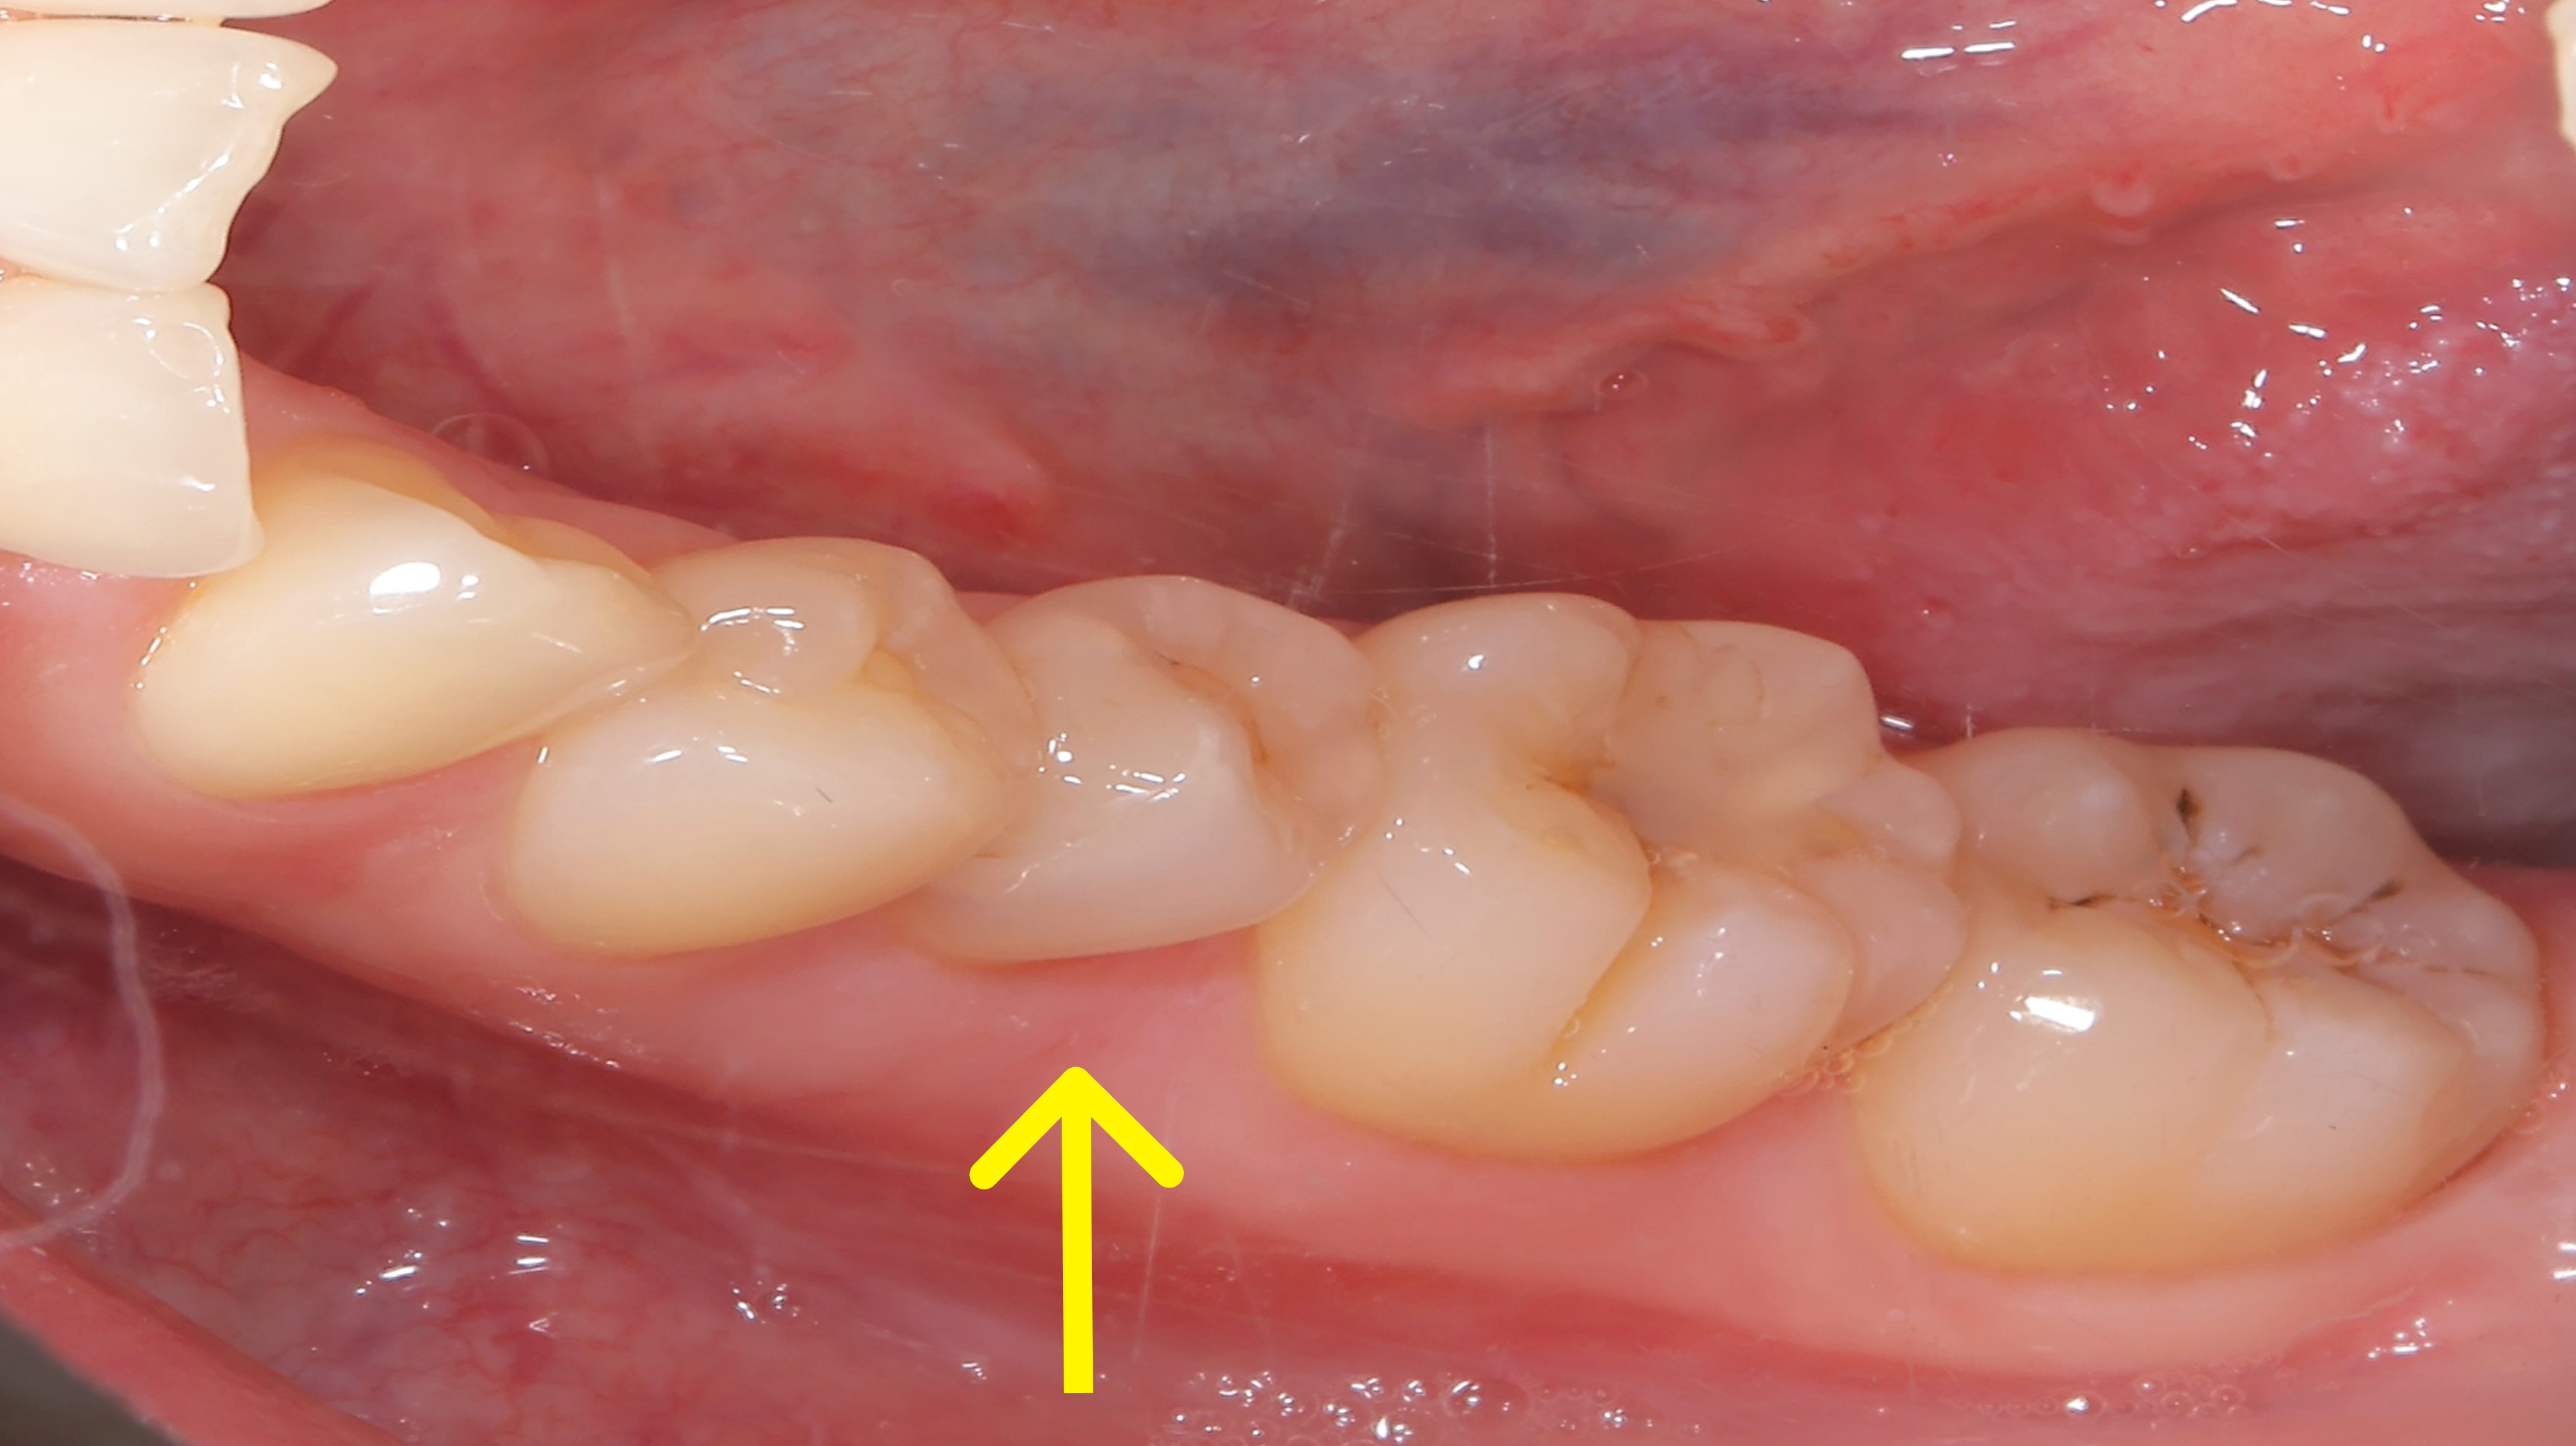

治療概要:矢印の歯は反対咬合(上の歯より下の歯の方が前に出ている)になっています。また、この方も過蓋咬合で下の前歯がほとんど見えません。

奥歯の噛み合わせはほとんど問題なく、マウスピース矯正を提案し矯正スタートしました。マウスピース矯正は食事中は外せたり、歯磨きもしっかりできるので良い治療法ですが、2番目の歯などあまり凹凸の少ない歯は動きが悪いことがあります。

行った治療

ほぼ他の歯が並んだ状態でも、やはりこの矢印の歯だけ動きが悪かったのと、左下の捻れた歯がなかなか治らなかったので、ワイヤーを部分的に使用させてもらいました。

下の写真が術前術後の比較です。下の前歯が見えるようになりました。上の前歯の傾きが変わるだけで口元の印象も変化します。